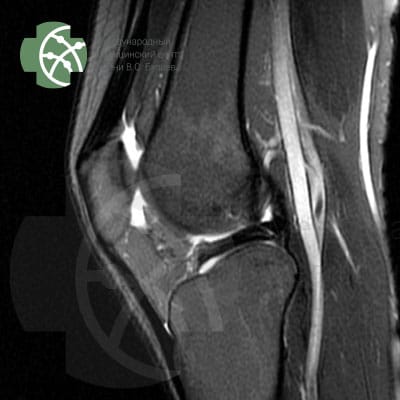

MRI of the knee joint

Magnetic resonance imaging of the knee joint without contrast agent

Our MRI knee joint protocol includes the following sequences:

Program / slice thickness

PD FS saggital 3 mm

T2 saggiati 3 mm

T2 FS saggital 3 mm

PD FS coronal 3 mm

T1 coronal 3 mm

PD FS axial 3 mm

MERGE saggital 3 mm